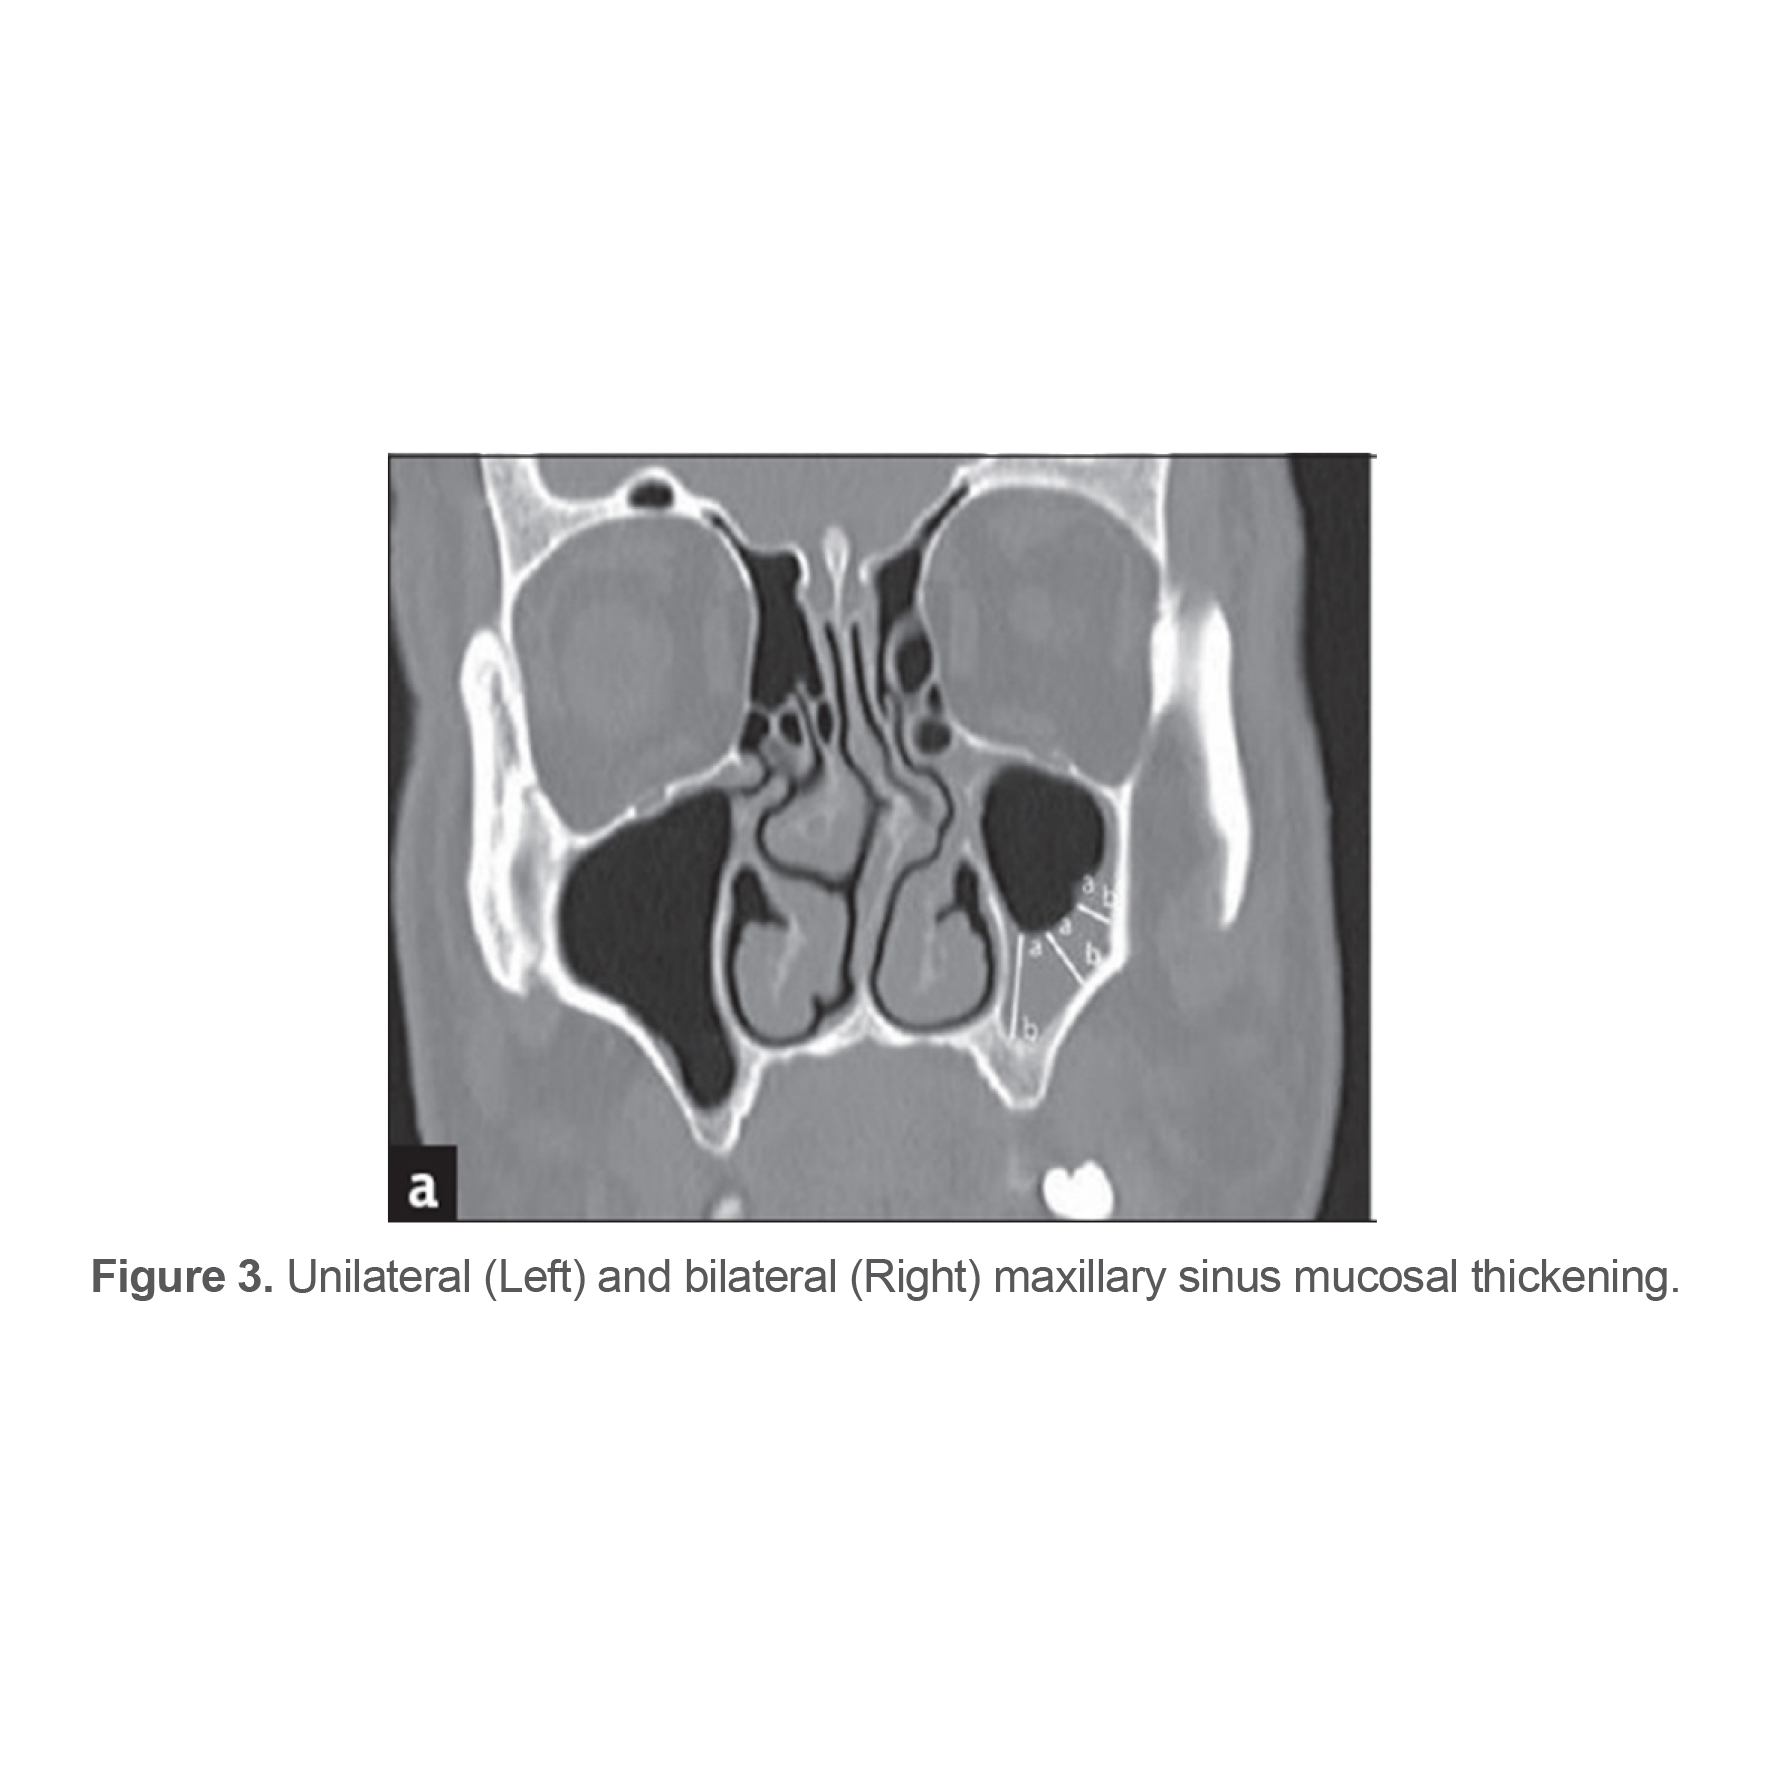

CB was considered as pneumatization of the middle concha of any size (Figure 1).

Figure 1. (Left) Concha bullosa on frontal view CBCT; (Right) Unilateral concha bullosa.